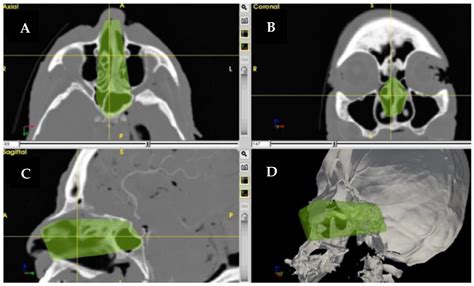

Computed Tomography (CT)

CT scans provide detailed images of the bony structures of the skull, making them an essential tool for evaluating the base of cranium. CT scans can detect fractures, dislocations, and other bony abnormalities. They are particularly useful in emergency settings, where quick and accurate diagnosis is crucial.